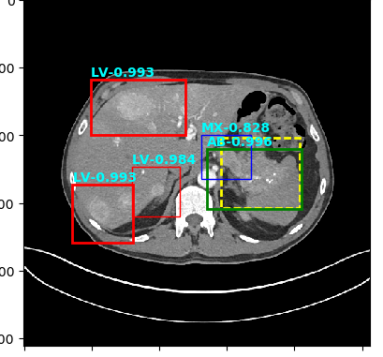

Figure 4: Six sample detection results are illustrated with the annotation lesion patches as yellow dashed boxes. The outputs from our proposed detection framework are shown in colored boxes with LiVer lesion (LV) in Red, Lung Nodule (LN) in Orange, ABdomen lesion (AB) in Green, Chest Lymph node (CL) in magenta and other MiXed lesions (MX) in blue. (a) Four lung lesions are all correctly detected; (b) Two lymph nodes in mediastinum is presented; (c) A Ground Glass Opacity (GGO) and a mass are detected in the lung; (d) An adrenal nodule; (e) Correct detections on both the small abdomen lymph node nearly aorta but also other metastases in liver and spleen; (f) Two liver metastasis are correctly detected. Three lung metastases are detected but erroneously classified as liver lesions .